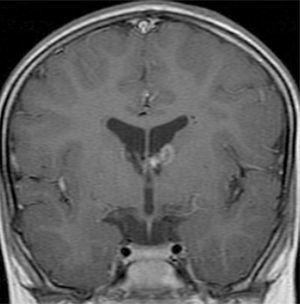

Las resonancias magnéticas (RM) cerebrales evaluadas han sido revisadas de forma independiente por el mismo examinador de la especialidad de Neurorradiología y se estudiaron las siguientes variables: número de tuberomas, localización supra o infratentorial, el número de lóbulos cerebrales con lesiones, el número y la lateralización de tuberomas con quistes, las líneas de migración radial de la sustancia blanca, los nódulos subependimarios y los astrocitomas de células gigantes. Los pacientes efectuaron los estudios de RM en equipos GE Signa 1.5T y en RM Philips Achieva 3.0T TX (3 pacientes), en el Departamento de Neurorradiología del CHP. Después de obtenida la imagen localizadora en el plano sagital, para identificar las comisuras anterior y posterior, se han adquirido imágenes en paralelo al plano intercomisural: FLAIR, T2 SE, T2 *, T1 SE y T1 SE tras contraste.

Para la identificación de tuberomas y líneas de migración radial han sido utilizadas imágenes FLAIR18 y para la identificación de los nódulos subependimarios, imágenes FLAIR y ponderadas en T2.

Se definió tuberoma como una lesión hiperintensa corticosubcortical en FLAIR y líneas de migración radiales como hiperintensidades lineales en FLAIR, que se extiende desde la superficie ventricular hasta el tuberoma cortical. Los nódulos subependimarios han sido investigados en cualquier ventrículo, con origen en la pared ventricular y con proyección hacia el interior de los mismos.

Se consideraron tuberomas con quistes subcorticales las lesiones con una señal similar al del líquido cefalorraquídeo en todas las ponderaciones y con un anillo hiperintenso alrededor en T2. Los tuberomas o nódulos subependimarios calcificados han presentado una hiposeñal en T2 y T2*. Una vez que la cantidad o el número de tuberomas en el parénquima encefálico son indicados como el mejor marcador de gravedad de epilepsia y de la función cognitiva1, se efectuó una evaluación cualitativa por medio la frecuencia de tuberomas. En cada lóbulo cerebral, la densidad de tuberomas se relaciona con la carga de lesión cerebral obtenida por la evaluación del número total de tuberomas y de la afectación de cada lóbulo por los tuberomas. Se consideró como elevada carga de lesión la afectación de todos los lóbulos por tuberomas, en pacientes con número total de tuberomas más de 15. No han sido evaluados la densidad o el volumen de tuberomas por técnica cuantitativa de segmentación automática de tuberomas por inaccesibilidad a software apropiado.

El 74,3% (26) de las RM disponibles han sido revisadas en todos los lóbulos cerebrales en el 76,9% (20) de los pacientes, en los cuales se identificaron más de 15 tuberomas, es decir, una elevada carga de lesión. En el 96,2% (25) de los enfermos se observaron líneas de migración radial (fig. 1). Estaban presentes nódulos subependimarios en el 84,6% (22), la mayoría de los cuales con calcificación y, en 3 casos, con captación de contraste (fig. 2). En el 23,1% (6) de los enfermos se encontraron tuberomas infratentoriales. Siete casos presentaban tuberomas con aspecto quístico (26,9%), 6 de los cuales en localización yuxtacortical y uno infratentorial (fig. 3). Es de referir un caso con probable astrocitoma de células gigantes, bajo control dimensional, en la región del agujero de Monro, sin signos de hidrocefalia (fig. 4). Ninguno de los enfermos presentaba atrofia focal.